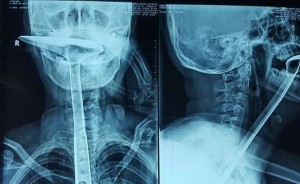

Sobrevive tras tragarse una espátula de cocina

Le dio un ataque de alergia y se le inflamaron las cuerdas vocales, se intentó aliviar con este utensilio y finalmente tuvo que ser operada. ¡Vaya susto! Escucha la historia en La Otra Realidad con Patricia Imaz y como se las gastan en la selectividad en China.